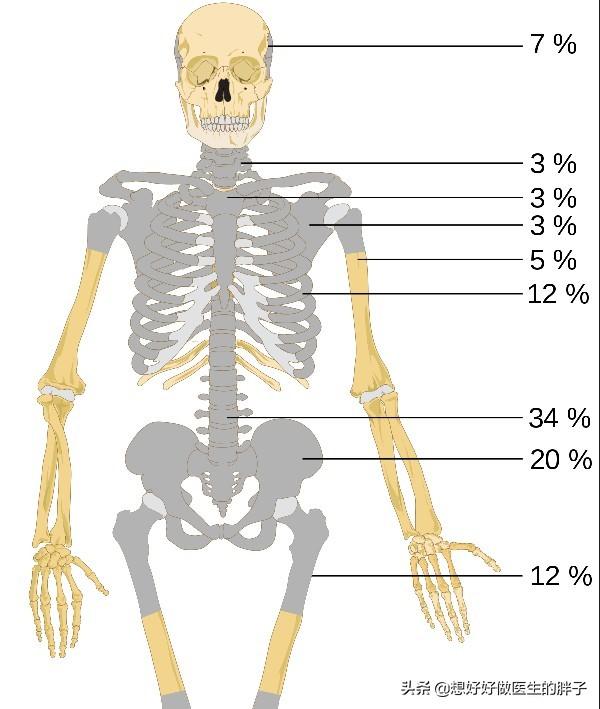

Les métastases osseuses survenant dans la colonne vertébrale sont les plus fréquentes (34 %), suivies par le bassin (20 %) et les os longs des membres inférieurs (12 %).。

- Les patients atteints de cancer ont des sites de métastases osseuses relativement favorables. La colonne vertébrale > le bassin > les os longs des membres inférieurs, les côtes > le crâne > les os longs des membres supérieurs.